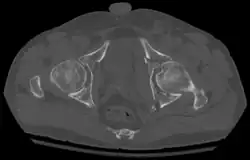

Axial CT image (viewed on bone windows) of a complex comminuted left acetabular fracture involving both anterior and posterior columns.